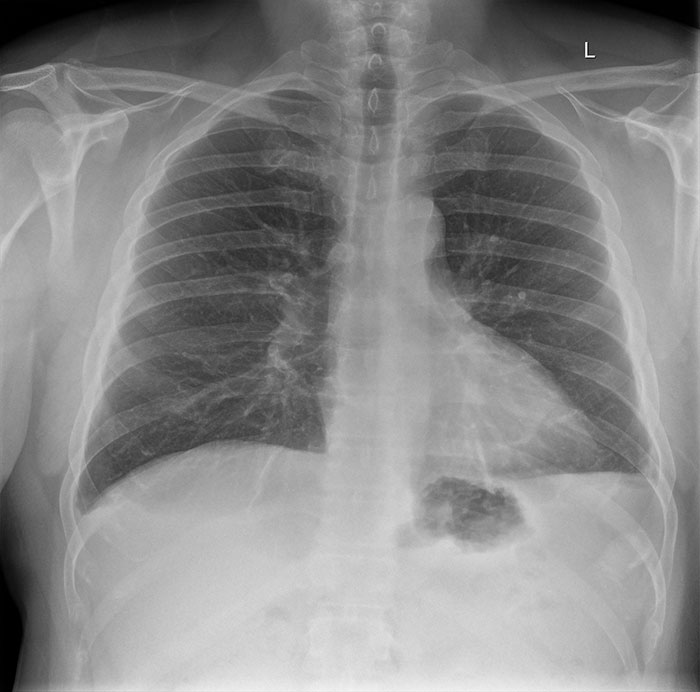

Christopher, who wrote the account under the username of Ispentwaytoolongthinkingaboutthis, is a 43-year-old living in the Toronto, Ontario area. The man told Bored Panda that he started having symptoms at the end of March and knew he had COVID-19 after reading what symptoms people who tested positive had. While he initially described his case as “minor,” Christopher later realized that his case was much more severe than he thought. “I called it a ‘minor’ case because that’s what I thought it was, but after reading many comments on my post, I know now it was a moderate to extreme case. I didn’t go to the emergency room earlier because I was scared and that was foolish. My experience was just short of extreme, I feel stupid not getting emergency help sooner, and the ER doctors I did see said a ventilator would most likely have been used if I had come in at my worst, as at that time my oxygen was only at 88% and should be 95% or better. I purchased an O2 monitor on Amazon in mid-March,” he said.

Christopher told us that the worst symptom for him was a burning sensation in his chest and difficulty breathing.

“The burning would come in waves over 7-10 days and the fatigue was nothing I’ve experienced before. I would say the burning feeling was an 8/10 on the pain scale. The fatigue was worst for me in the evening between 7-10 pm. The brain fog was bad as well. It was like my IQ was dwindling by the day. A horrible experience to live with for weeks on end.”

After 6 long weeks of battling the disease, Christopher says he’s doing much better; however, he’s still not fully recovered. “I would say I am at 75% currently and at my worst I’d say I was at 20%. After 6 weeks, I still have breathing issues and still have the slight ‘burning’ and heaviness in the top of my chest. It comes and goes, but at night, it’s far worse. I can feel I’m on the mend but also can feel it will be a long road to full recovery. My only main concern now is any long-term damage I may suffer, but time will tell.”